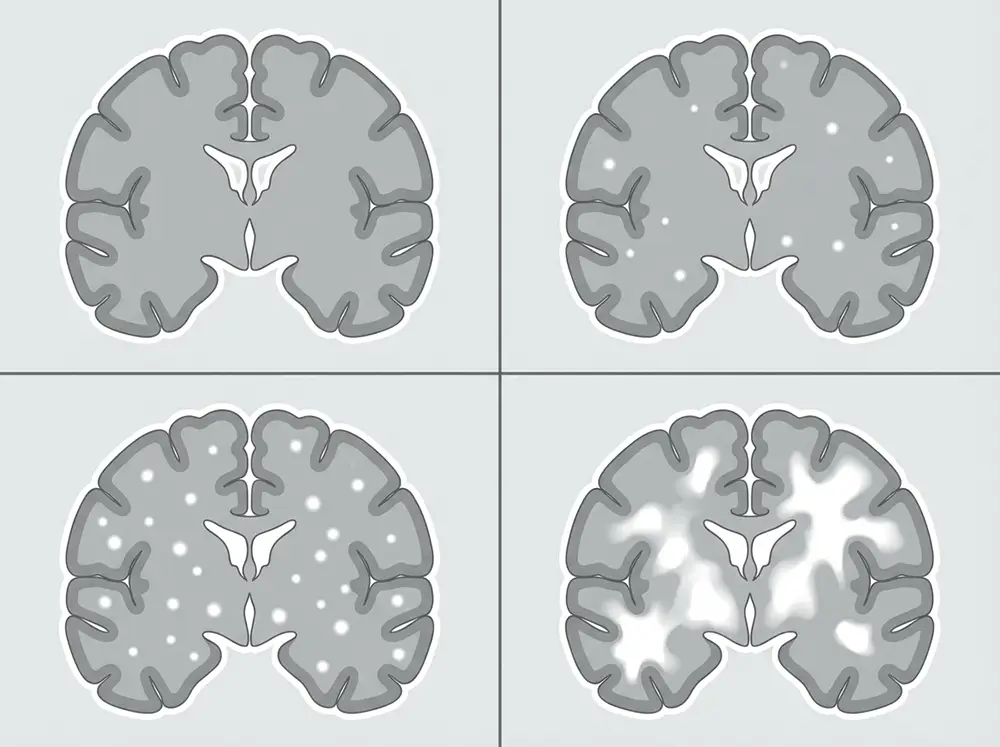

L’échelle de Fazekas : interpréter son score

Pour quantifier et classer les lésions de la substance blanche observées à l’IRM, les neuroradiologues utilisent l’échelle de Fazekas, mise au point en 1987 par le neurologue László Fazekas. C’est l’outil de référence international pour évaluer la sévérité de la leucopathie vasculaire. Elle distingue deux types de lésions — les hypersignaux périventriculaires (autour des ventricules cérébraux) et les lésions de la substance blanche profonde ou sous-corticale — et les classe en quatre grades :

| Score Fazekas | Lésions périventriculaires | Lésions de la substance blanche profonde | Signification clinique |

|---|---|---|---|

| 0 | Aucune lésion | Aucune lésion | Absence d’anomalie |

| 1 | Points ou fines lignes isolés | Foyers ponctuels isolés | Atteinte légère, souvent asymptomatique |

| 2 | Halo régulier autour des ventricules | Début de confluence des lésions | Atteinte modérée, premiers symptômes possibles |

| 3 | Hypersignal irrégulier s’étendant en profondeur | Zones confluentes étendues | Atteinte sévère, symptômes souvent présents |

Ce score est un repère standardisé et validé scientifiquement, qui permet au clinicien de suivre l’évolution des lésions dans le temps et d’adapter la prise en charge. Il faut cependant rappeler qu’un même score peut recouvrir des situations cliniques très différentes selon le patient.